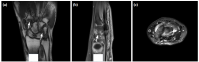

The degree of BE and synovial hyperplasia in SNRA or SPRA is more serious, and the blood flow signal is more abundant. However, the degree of synovial hyperplasia in osteoarthritis was mild, and no obvious blood flow signal was detected (Figures 1, 2, 3 and 4). Magnetic resonance imaging (MRI) studies of SPRA also showed serious BE (Figure 5).

One of the limitations to this study is the lack of other imaging and pathological comparisons. Magnetic resonance imaging is an effective tool to examine early RA and to evaluate therapeutic effect; it is considered gold standard for RA research. However, in practice, it is time-consuming to perform MRI examinations on all the affected joints of the patient's hands. Moreover, MRI can be costly for many patients. On the other hand, although needle biopsy of joint synovium is helpful for accurate diagnosis of disease, it is an invasive operation with high technical requirements for the operator and may, thus, not be the best choice for patients.